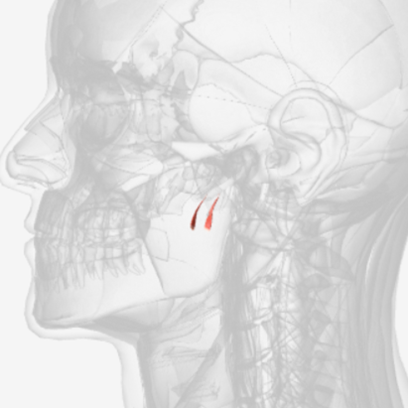

Levator veli palatini

origin is on the petrous portion of the temporal bone, coursing down and forward to insert on the palatal aponeurosis of the soft palate; function elevates and retracts the posterior velum

Levator Veli Palatine

Levator veli palatini

E

Levator veli palatini

B